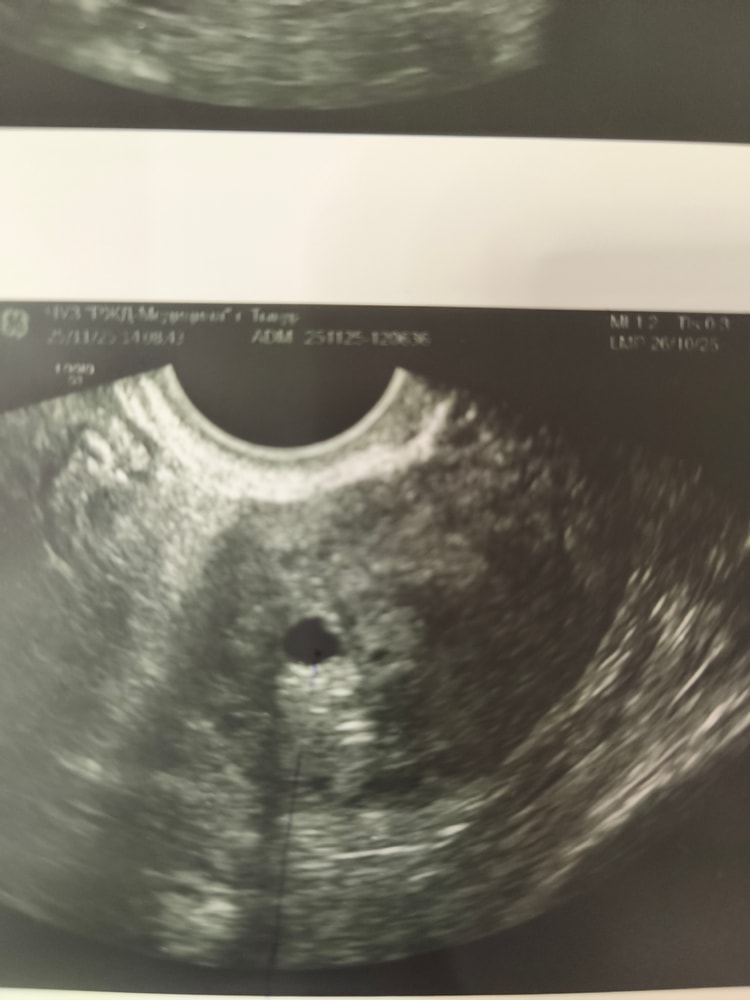

Джеллибин, вот сейчас я вам покажу, они даже с разных сторон находятся Изображение Это сегодня , ниже в первый день задержки Изображение

0

Джеллибин, я вообще сомневаюсь что в первый день задержки они увидели пя, это было 15 дпо, овуляция отслеживала по узи. У меня аденомиоз, я уже не понимаю, что они видят и чего нет

Буду трижды мамой в этом году, отправляют из за того что нет желточного мешочка и деформировано пя